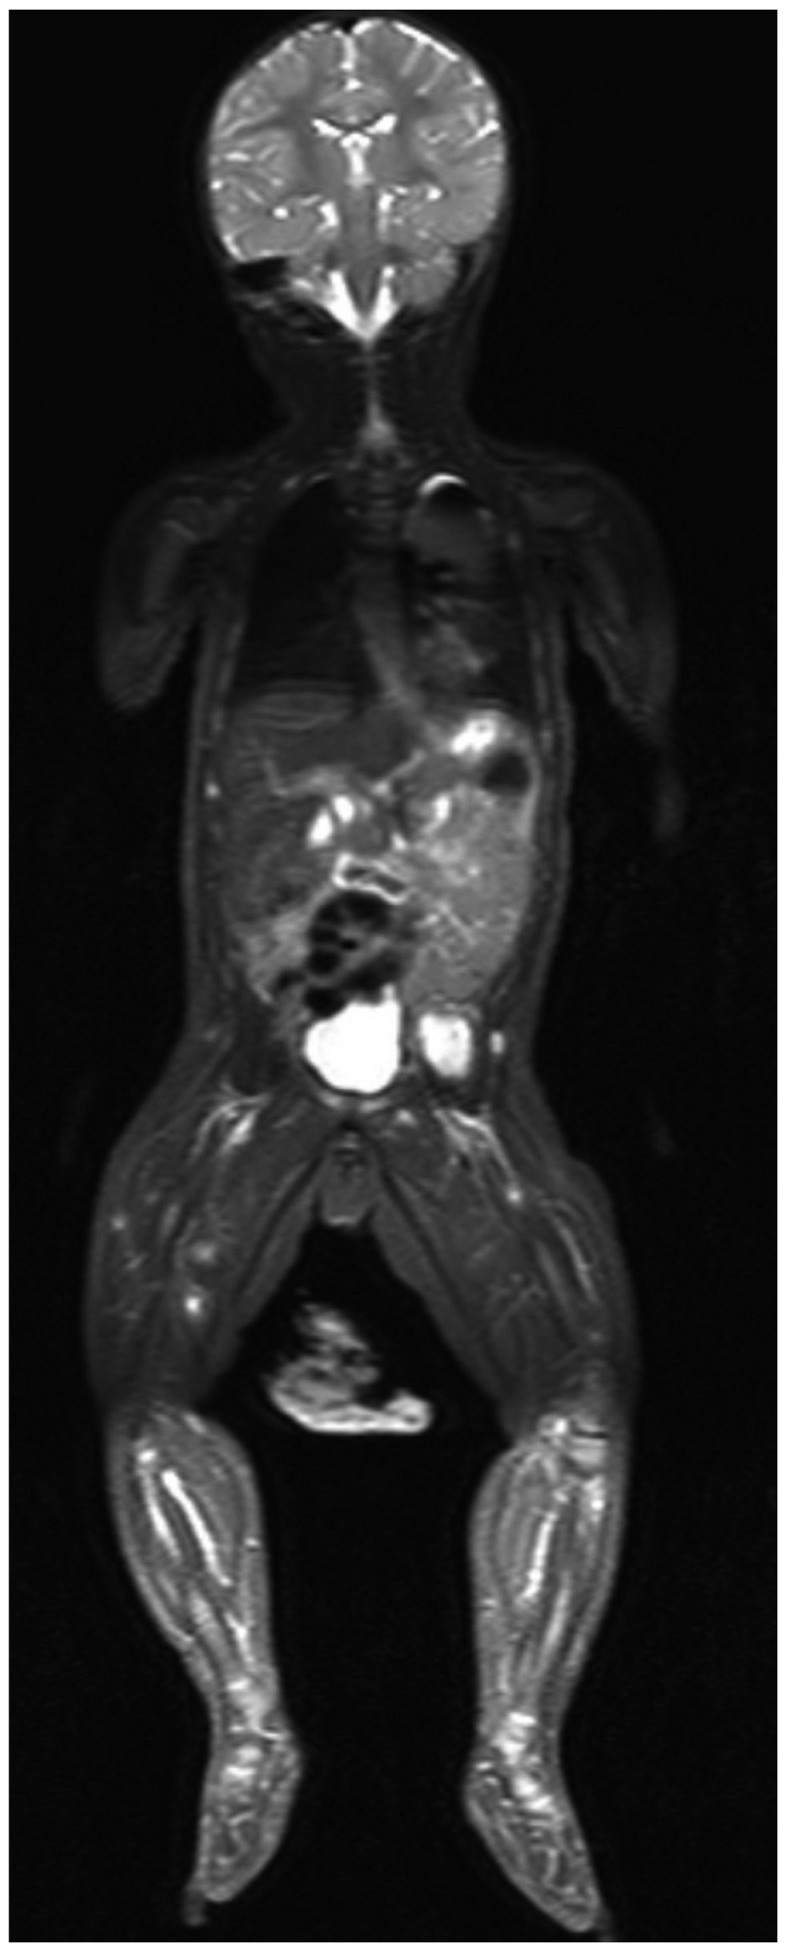

Whole-body MRI was performed for panoramic localization of the nodules using short TI inversion recovery (STIR) and diffusion-weighted whole-body imaging with background body signal suppression (DWIBS) sequences in the coronal or axial planes and volumetric 3D reformatting, to provide a detailed assessment of the lesions and an accurate estimation of the disease status.

The MRI revealed a significant number of nodules (~70 lesions), with almost exclusive muscle localization, in the head, trunk, abdomen, and upper and lower limbs.

STIR revealed multiple widespread lesions, characterized by a hyperintense core, surrounded by a rim of low signal (Fig. 1). The largest lesion was detected in the left iliopsoas muscle (34×26×20 mm), whereas no compression or infiltration of adjacent tissues was observed, other than mild ureteral compression.

Figure 1.

Short T1 inversion recovery sequence, coronal plane. The largest lesion was located in the left iliopsoas muscle, with multiple smaller masses in the lower limbs. The lesions display a hyperintense core with a lower/intermediate peripheral intensity.